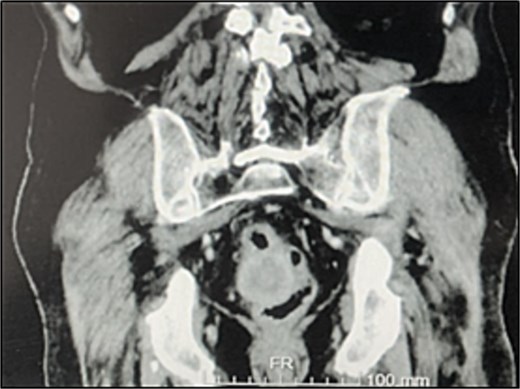

A contrast-enhanced chest-abdominal-pelvic computed tomography (CT) scan revealed a solid, multilobular mass, with approximately 8 × 6 × 8 cm, likely originating from the SB, with asymmetric wall thickening, heterogeneous contrast enhancement, areas consistent with necrosis and central calcification (Figs 1 and 2), suggestive of GIST. Simultaneously, a solid nodular lesion was identified on the anterior wall of the rectum, exhibiting exophytic growth with a heterogeneous texture, well-defined borders and measuring 5 × 3 cm, without adjacent fat infiltration, raising suspicion of another GIST (Fig. 3).